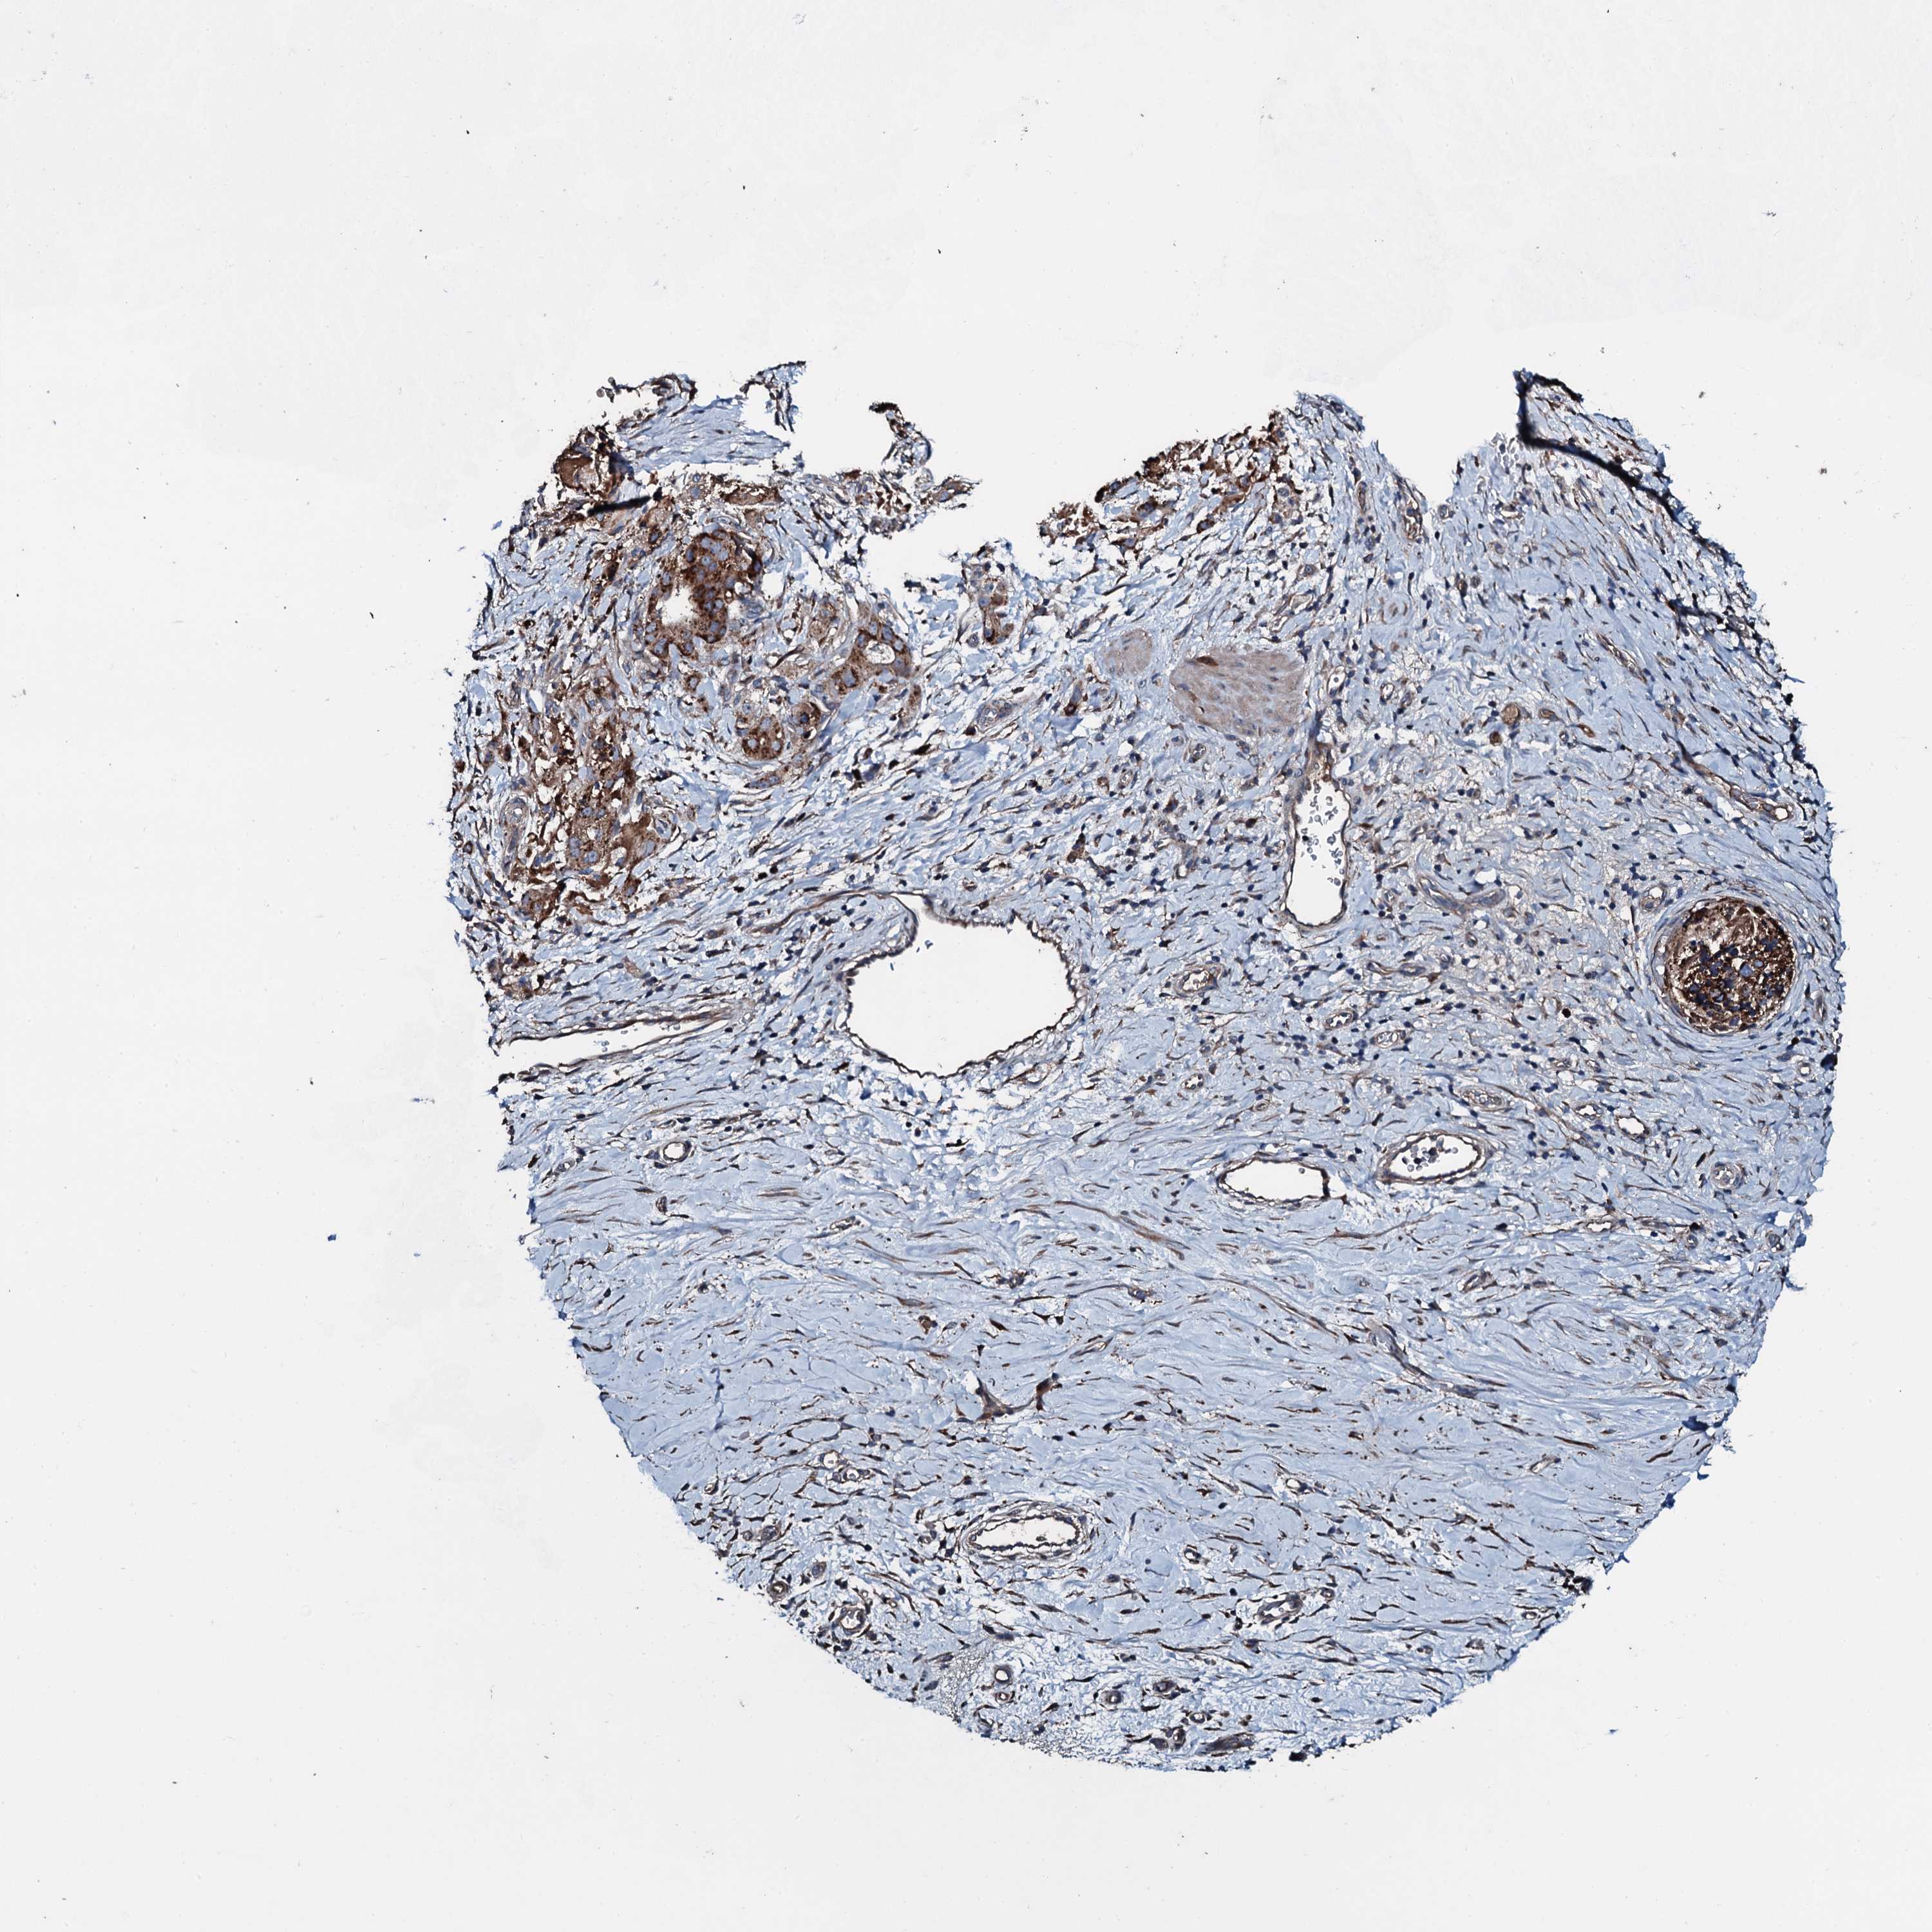

STOMACH CANCER - Protein expressioni

A mouse-over function shows sample information and annotation data. Click on an image to view it in a full screen mode. Samples can be filtered based on level of antibody staining by selecting one or several of the following categories: high, medium, low and not detected. The assay and annotation is described here.

Note that samples used for immunohistochemistry by the Human Protein Atlas do not correspond to samples in the TCGA dataset.

Antibody stainingi

Antibody staining in the annotated cell types in the current human tissue is reported as not detected, low, medium, or high, based on conventional immunohistochemistry profiling in selected tissues. This score is based on the combination of the staining intensity and fraction of stained cells.

Each image is clickable and will lead to virtual microscopy that enables deeper exploration of all samples and also displays staining intensity scores, fraction scores and subcellular localization as well as patient and tissue information for each sample.

Antibody HPA040870

Staining

High

Medium

Low

Not detected

Intensity

Strong

Moderate

Weak

Negative

Quantity

>75%

75%-25%

<25%

None

Location

Nuclear

Cytoplasmic/membranous

Cytoplasmic/membranous,nuclear

Adenocarcinoma, NOS